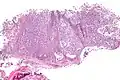

| Micrograph of a myoepithelioma. H&E stain. | |

The myoepithelial cells may be spindled, plasmacytoid, eithelioid or clear. Tubules or epithelium are absent, or present in a small amount (<5%) by definition. Tumours with myoepithelial cells and a large amount of tubules are classified as pleomorphic adenomas (which must also contain the characteristic chondromyxoid stroma, which is normally absent in myoepithelioma).